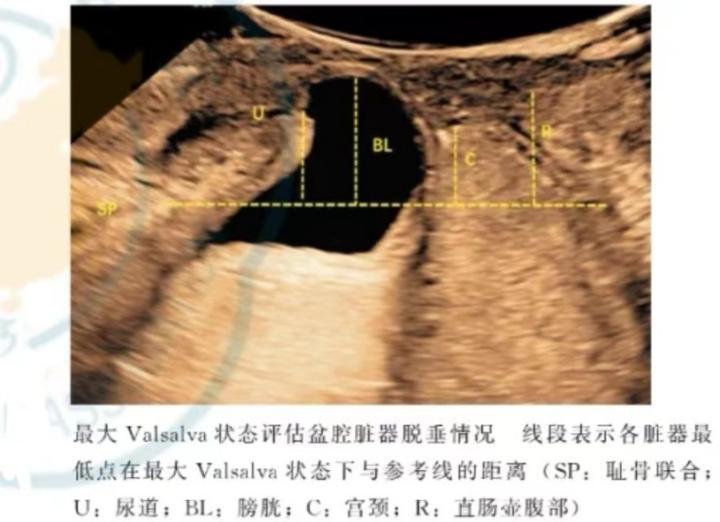

盆底超声是将探头放于会阴部或阴道内,通过指导患者正确的完成缩肛和 Valsalva 动作,动态观察盆腔脏器的位置变化,从而判断盆腔脏器的脱垂情况及盆底肌肉的完整性。

盆底三维成像技术还可以获得完整的肛提肌裂孔的立体声像图,准确测量裂孔大小,直观地观察肛提肌及韧带走形及损伤程度。盆底超声被广泛应用于盆底功能障碍性疾病的诊断和治疗后疗效的评估。